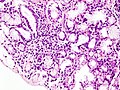

Features (salivary gland):[3]

- "Significant lymphocytic infiltrate" adjacent to viable salivary gland (or lacrimal gland) acini - key feature.

- "Significant lymphocytic infiltrate": cluster of >= 50 lymphocytes - important.

- Lymphocytes may be perivascular or periductular.[4][5]

- Plasma cells should not exceed 10% of the inflammatory infiltrate.[4]

- May have "benign lymphoepithelial lesions"[6] - intraepithelial lymphocytes.

- +/-Fibrosis.

SS - low mag. (WC)